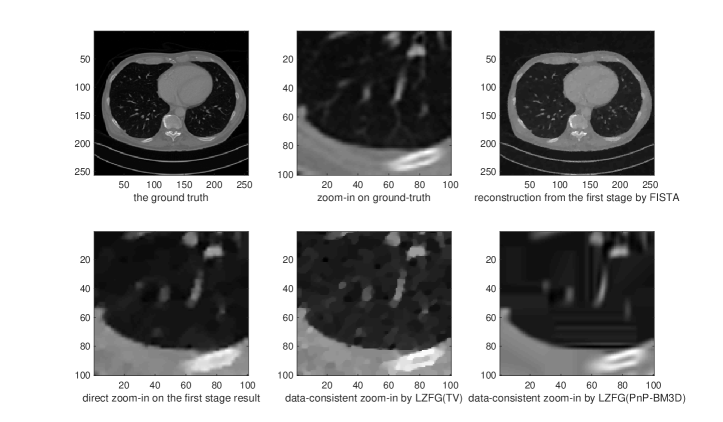

As we can observe, the reconstructed image has a reasonable quality, but could oversmooth some of the local areas which may need to be refined and zoomed in. This observartion suggest that although the regularization can be optimized to provide the best PSNR globally, classical iterative methods indeed have such a limitation for not taking care of local reconstruction performance. In this example we seek to zoom-in 4 times larger a by block of a by first-stage image. Hence the global iterative superresolution of the whole image will be 25 times more expensive than our approach in this setting. Direct zoom-in on this block would often have poor performance since it does not re-utilize the measurement data. We then test two instants of our LZFG framework. For the first one we use TV regularization while for the second one we use BM3D denoiser (Dabov et al., 2007). We use the MATLAB imresize function as the up-sampling and down-sampling operators, with the default bicubic interpolation.

We present in Figure 2, 3, 4, and 5 four examples of local zoom-in. We can observe from the numerical results that our method can indeed recover the details of the local blocks with high-quality. The direct zoom-in from the first-stage reconstruction fails to recover local details missed from the first-stage reconstruction since it does not utilize the measurement data, demonstrating the importance of data-consistency in local zoom-in of medical images. We present the convergence curves of LZFG with TV and BM3D in Figure 1 reporting the PSNR results towards the zoomed-in ground-truth image. From the PSNR result we can observe that our methods provide significantly improved reconstruction accuracy (5 to 10 dB better) compared to the naive approach.